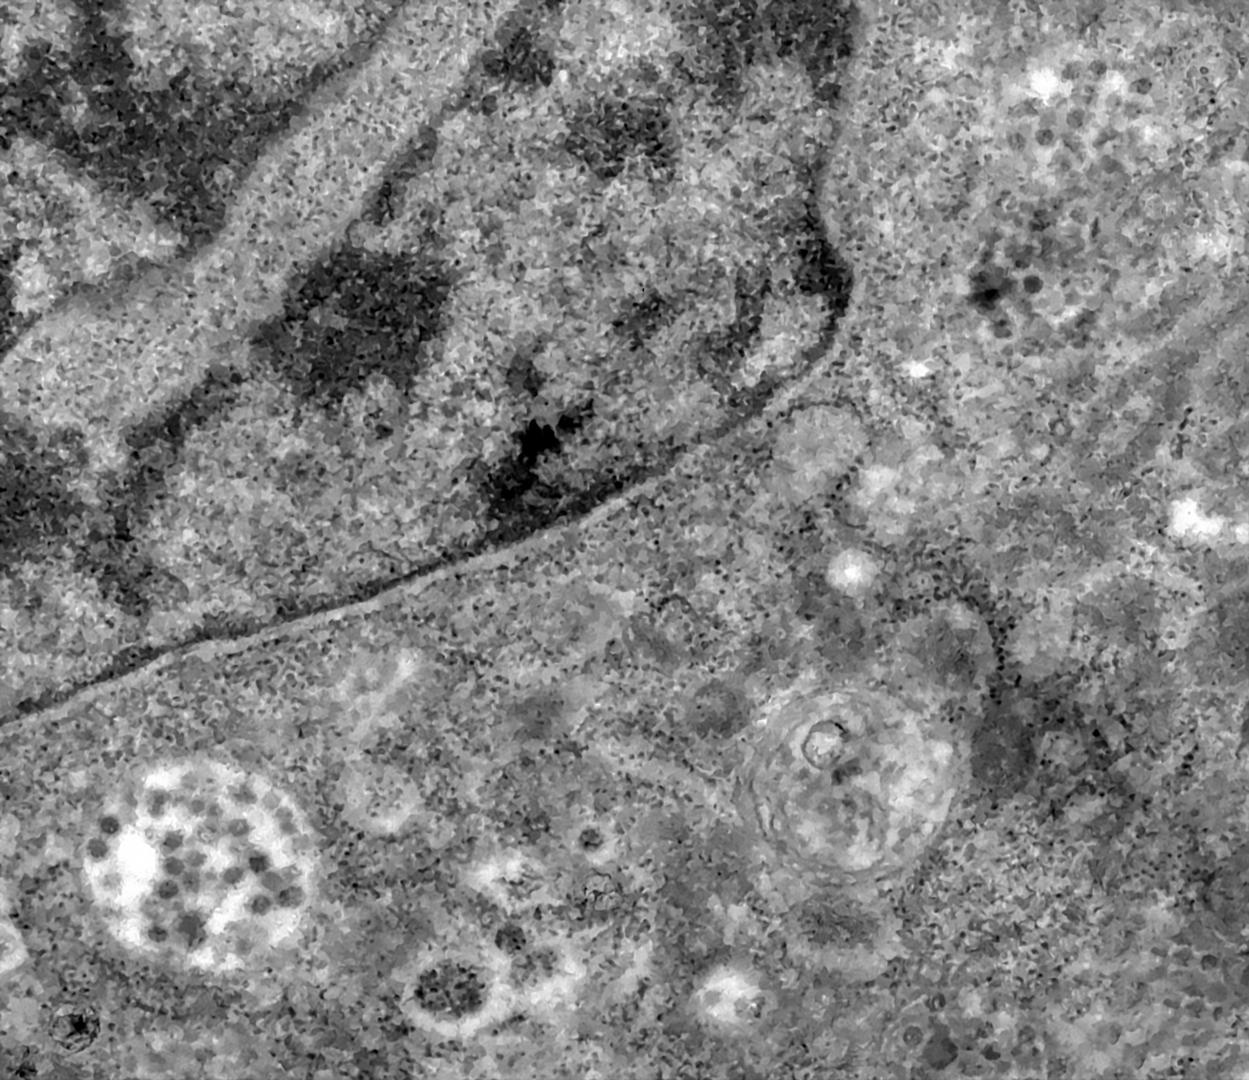

Koristeći se transmisijskim elektronskim mikroskopom, znanstvenici brazilskog Instituta Oswaldo Cruz uspjeli su snimiti točan trenutak u kojem novi koronavirus SARS-CoV-2 uspijeva zaraziti stanicu nakon što je prošao kroz njezinu ovojnicu.

U svojem priopćenju brazilski znanstvenici navode kako su se za pokus koristili virusom izoliranim iz uzorka prikupljenog brisom nosa i grla zaražene osobe. Tako se na slici snimljenoj mikroskopom koji uvećava i do dva milijuna puta vidi kako nekoliko čestica novog koronavirusa, to su prikazane zatamnjene čestice, prilazi stanici, prolazi kroz staničnu membranu i ulazi u citoplazmu.

To je trenutak kada je osoba zaražena koronavirusom. SARS-CoV-2, kao i ostali koronavirusi, jest RNA virus, što znači da se replicira u citoplazmi. Na kraju je stanica uništena, a virus nastavlja inficirati susjedne stanice na isti način. Koronavirusi su grupa ovijenih, nesegmentiranih RNA virusa koji pripadaju obitelji Coronaviridae, red Nidovirales, navedeno je na stranici plivazdravlje.hr, .

Cijela skupina virusa dobila je ime jer su nalik na krunu (corona je latinska riječ za krunu) zbog batićastih nastavaka koji strše izvan virusne ovojnice, a vidljivi su pod elektronskim mikroskopom. Široko su rasprostranjeni među ljudima i drugim sisavcima, a može se očekivati otkriće novih virusa iz obitelji Coronaviridae i u budućnosti.